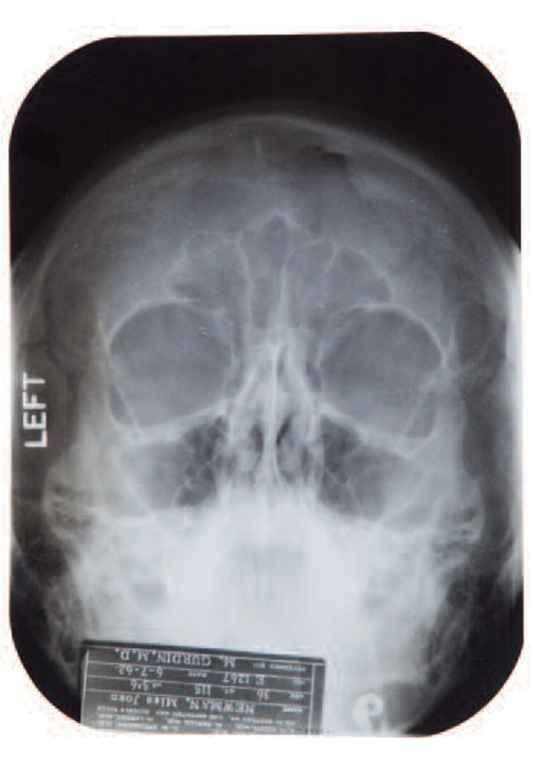

Il pettegolezzo sul ricorso al bisturi sembra infatti trovare conferma dagli appunti di un medico, il defunto dott. Michael Gurdin. Una sorta di ‘cartella sanitaria’ dell’attrice, con tanto di lastre, in cui si fa riferimento ad un intervento estetico al mento e ad una rinoplastica effettuata nel 1950.

I raggi X sono invece del 7 giugno 1962, due mesi prima della sua morte, avvenuta all’eta’ di 36 anni per un’overdose di barbiturici. Le lastre al cranio, alle ossa nasali e al palato, insieme alla documentazione sanitaria della star americana, saranno messe all’asta a Beverly Hills, in California, il prossimo 9 novembre. La base di partenza e’ tra i 15 e i 20 mila dollari.